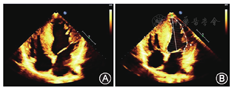

患者男性,15岁,因"发热伴头晕6 d"于2014年5月18日来我院就诊。患者于入院前6 d无明显诱因出现发热,体温最高达38.5 ℃,伴咳嗽咳痰,头晕,乏力,恶心呕吐,呕吐物为胃内容物,无胸痛、胸闷,无肩背部放射痛,无头痛,无意识丧失,就诊于当地医院,给予抗感染、抑酸等治疗,体温恢复正常,仍间断出现头晕、恶心呕吐。遂来我院就诊。患者自幼体弱,易感冒,体力较正常同龄者差,活动后易出现心悸、乏力、气喘,读书成绩不及格。入院时体检:智力低,发育差,身高160 cm,体重42 kg。双肺呼吸音粗,未闻及干、湿性啰音,心律齐,各瓣膜听诊区未闻及杂音,肝于肋下4 cm、剑突下5 cm可触及,脾肋下未触及。双上肢近端肌力Ⅴ级,双下肢近端肌力Ⅳ+级,远端肌力Ⅴ级。四肢腱反射减弱,病理征阴性。家族史:父母及姐姐体健,家族中其他成员无类似疾病。入院后主要生化检查:肌酸激酶2 626 U/L(正常值38~174 U/L),肌红蛋白1453 ng/ml(正常值0~85 ng/ml),肌酸激酶同工酶62.3U/L(正常值0~24.0 U/L),乳酸脱氢酶1 718 U/L(正常值120~300 U/L), ALT 1 043 U/L(正常值9~50 U/L),AST 882 U/L(正常值15~40 U/L)。抗核抗体、抗U1核糖核蛋白、抗Sm、抗SSA、抗SSB、抗Scl-70、抗Jo-1、抗r核糖核蛋白、抗双链DNA抗体均为阴性。类风湿因子、抗链球菌溶血素O、抗环瓜氨酸肽抗体呈阴性。肝炎筛查+戊型肝炎抗体测定结果为阴性。EB病毒、单纯疱疹病毒Ⅰ型及人巨细胞病毒核酸检测阴性。梅毒螺旋体抗体和人类免疫缺陷病毒抗体阴性。红细胞沉降率7 mm/h(正常值<15 mm/h),C反应蛋白13.1 mg/L(正常值0~8.0 mg/L),第三代促甲状腺素、总三碘甲状腺原氨酸、总甲状腺素、游离甲状腺素及游离三碘甲状腺原氨酸水平正常。辅助检查:胸部+全腹CT结果示:(1)全心增大,肺动脉增粗,宽径约3.5 cm;(2)两肺上叶可见多发斑片状密度增高影,以左肺上叶为主,边缘模糊考虑炎症;(3)心包积液,右侧胸腔少量积液;(4)肝脏增大,腹腔积液。心脏超声结果示:(1)室间隔非对称性肥厚(图1A),右心室壁及右心室节制索肥厚(图1B),考虑肥厚性心肌病;(2)二、三尖瓣轻中度关闭不全;(3)左心室正后壁基底段、中段及下壁基底段运动消失;(4)左心室收缩功能减低、舒张功能异常(Ⅲ度,限制性充盈),左心室充盈压增高;(5)右心室收缩功能及整体功能减低;(6)少量心包积液。心电图示:窦性心律,预激综合征图形,心率78次/min,Ⅰ、Ⅱ、Ⅲ、aVF、aVl、V1-6导联ST段压低,T波倒置。24 h动态心电图结果:窦性心律,平均心率为76次/min,最小心率55次/min,最大心率111次/min。室性早搏140个,呈单发、成对及室性心动过速。室上性早搏99个,呈单发、成对及房性心动过速。无心室停搏。ST-T段异常。肌电图示被检双胫前肌、右股三头肌、右三角肌呈肌源性损害。肱二头肌肌肉活体组织检查HE染色可见肌束内结缔组织无明显增生,肌间小血管壁无增厚,未见炎性细胞浸润。部分肌纤维胞质内有典型自噬空泡形成(图2A),胞质内可见不规则形状的嗜碱性物质沉积,肌纤维大小不等,直径20~50 μm,未见肌纤维变性,无核内移增加,未见不透明纤维和环状纤维。改良Gomori三色染色可见空泡样肌纤维(图2B),部分胞质内可见蓝紫色物质沉积。四氮唑还原酶染色和琥珀酸脱氢酶染色可见部分区域氧化酶缺失及中央轴空样肌纤维。非特异性酯酶染色可见空泡区域酶活性增强,部分肌纤维内可见棕黑色物质沉积(图2C)。酸性磷酸酶染色未见明显异常。油红O染色示个别肌纤维脂滴增多。过碘酸希夫染色部分肌纤维内阳性物质不均匀沉积(图2D)。ATP酶染色显示两型肌纤维呈镶嵌排列。免疫组织化学分析提示:肌纤维dystrophin(+),dysferlin(+),sarcoglycan(+)c-dystrophiny和α-sarcoglycan染色可见肌细胞内膜性自噬空泡形成(图2E、图2F)。电镜观察显示肌纤维内出现大量的膜性空泡,部分空泡内存在大量糖原颗粒、溶酶体颗粒以及自噬碎片,空泡周围有散在分布的糖原颗粒(图3A、图3B)。初步考虑为糖原贮积症、Danon病可能。蛋白质印迹证实lamp2蛋白缺失,送检肌肉标本进行LAMP2基因突变检测。检测结果:在LOVD数据库进行检索分析,送检标本LAMP2基因外显子4发现序列异常,c.467_470delTATCinsG,该改变尚无报道,属于移码突变(图4),该位点改变可导致编码氨基酸提前终止,正常人群中无此突变,临床意义明确,证实患者为Danon病。然而由于家属经济以及其他原因,未能进一步对患者基因进行家系验证,明确发病风险。追踪回访患者,令人遗憾的是患者出院仅半个月猝死,患者母亲偶感心悸,无其他不适。